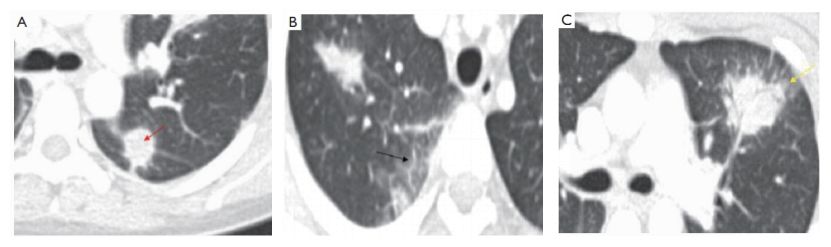

4. 圆形磨玻璃影型

A、红箭-左肺上叶可见一软组织密度结节,显著强化;

B、黑箭-右肺下叶可见增厚的小叶间隔;

C、结节边缘不规则、可见长毛刺,周围可见明显的晕征,可见血管集束征,并且部分牵拉临近胸膜导致胸膜增厚。